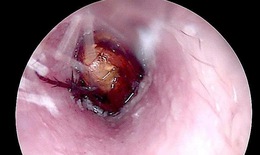

Cụ ông 90 tuổi nguy kịch sau bữa cơm tối

Camera bệnh viện - 06/10/2025 17:07SKĐS - Bệnh viện Bệnh Nhiệt đới Trung ương vừa cứu sống thành công cụ ông N.V.S (90 tuổi, ở Hà Nội) bị tắc nghẽn đường thở trong lúc ăn tối.